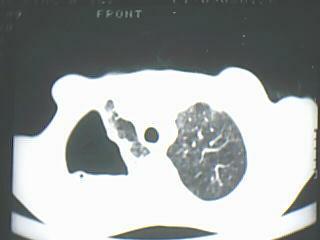

以下是引用随光逐影在2009-8-7 15:40:00的发言:[br]考虑右肺继发性肺结核并右肺上叶空洞形成,两肺支气管播散;不排除右肺上叶空洞内霉菌感染可能。

以下是引用jiangjing在2009-8-7 14:38:00的发言:[br]右上肺张力空洞,酐珞坏死灶,支气管扩张,多发播散灶,纵膈淋巴结显示,胸膜增厚---结核